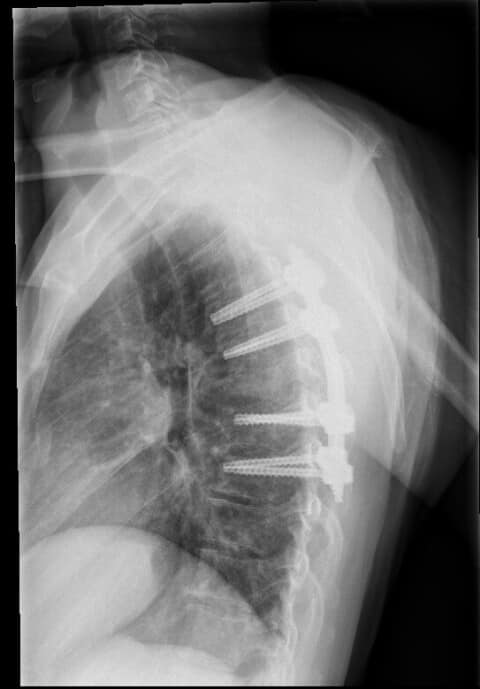

1. Mugurkaula krūšu daļas lūzuma stabilizācija perkutāni mazinvazīvi t.i. stabilizējošās skrūves un stieņi tika implantēti caur atsevišķiem maziem griezieniem, nevis plaši atverot brūci. 2. Mugurkaula otrā kakla skriemeļa stabilizācija ar speciālu pielāgotu kompresijas skrūvi.

Mazinvazīvā metode, kad operācija pacientam tiek veikta caur vairākiem nelieliem griezieniem, TOS tiek praktizēta jau daudzus gadus, tomēr šāda veida operācija, kad vienam pacientam tiek vienlaicīgi maztraumatiski izoperēts un nofiksēts gan mugurkaula kakla daļas skriemeļa lūzums, gan mugurkaula krūšu daļas nestabils lūzums, ir notikusi Latvijā pirmo reizi, stāsta TOS.